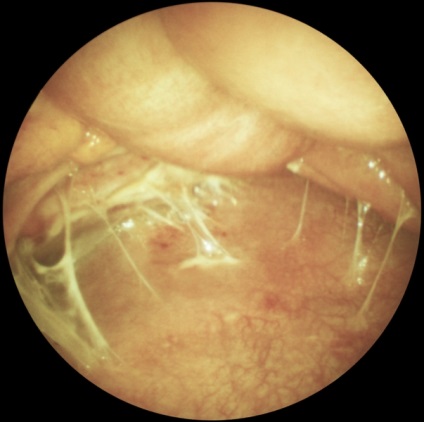

Laparoszkópia nőgyógyászat diagnosztikai és terápiás lehet előállítani bevezetésével laparoszkóp a hasfalon keresztül, vagy egy bemetszésen keresztül a posterior vaginális boltozatot (culdoscopy). Javallatok sürgősségi tartja az AL a nőgyógyászati gyakorlatban is gyanús petevezeték terhesség. piosalninks, apoplexia vagy petefészek ciszta, méh perforáció, és így tovább. d. A rutinszerűen elvégzett L. (culdoscopy) hosszan tartó kismedencei fájdalom ismeretlen etiológiájú, algomenoree súlyos, nehezen gyógyítható a szokásos orvosi terápiás módszerek gyanúja belső nemi rendellenességek és más szervekben. Contra L. hajtjuk a hasfalon keresztül ugyanazok, mint az L. vállalta, hogy vizsgálatát a hasüregbe. Culdoscopy ellenjavallt a súlyos összenövések pozadimatochnom térben a tumorokat a medence. Laparoszkópos kép savós petefészek ciszta ábrán látható. 4, valamint. Laparoszkópia is végezni néhány terápiás tevékenység: koaguláció és boncolása összenövések (. 4. ábra, b, c), endokoagulyatsiyu heterotopical gócok endometriumbiopszia petefészek punkció retenciós ciszták és mások.

Ábra. 4b). Laparoszkópos képet néhány nőgyógyászati betegségek - összenövések kismedencei folyamat.

Ábra. 4c). Laparoszkópos képet néhány nőgyógyászati betegségek - orális forma kismedencei összenövések után laparoszkópos boncolás.